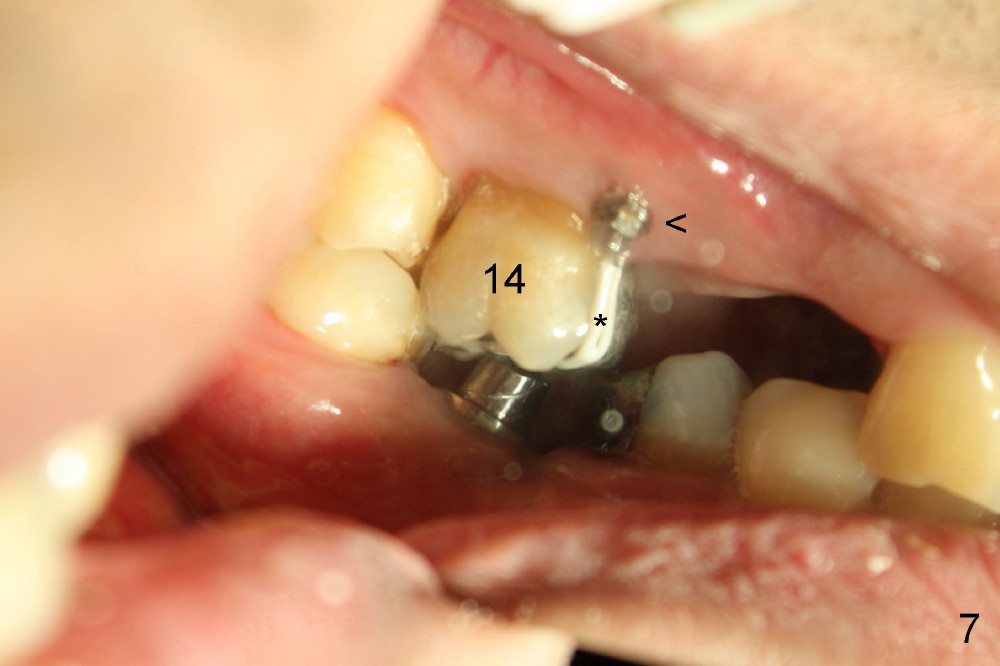

给植牙(图四箭头)装上4.5(直径)x5 (高度)mm基牙(A)时,病人咬合不对:上下第二磨牙(#15, 18)之间有空间。直感基牙太长了,必须磨短,但是磨短坚硬的钛合金基牙,可不容易,而且这次要磨除不少,越磨越老火(upset),突然意识到自己犯一个严重错误。终于上下牙齿能碰到(图五镜影像mirror image),但是还没有足够间隙为植牙制作牙冠。这时很容易看出上颌第一磨牙往下面伸长(图五),如果再磨短基牙,牙冠固位可能不好,所以唯一方法便是把上颌第一磨牙往上面压(intrusion),需要做牙齿矫正,而且使用微型植牙(图五至图七箭头;*:橡皮筋持续牵引磨牙往上移动)。